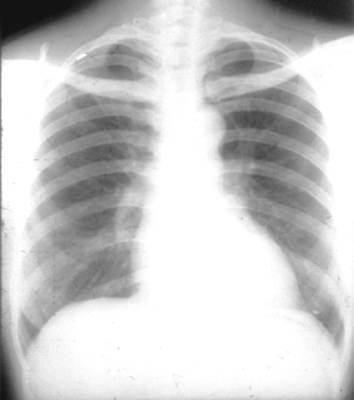

正常心脏左侧位片